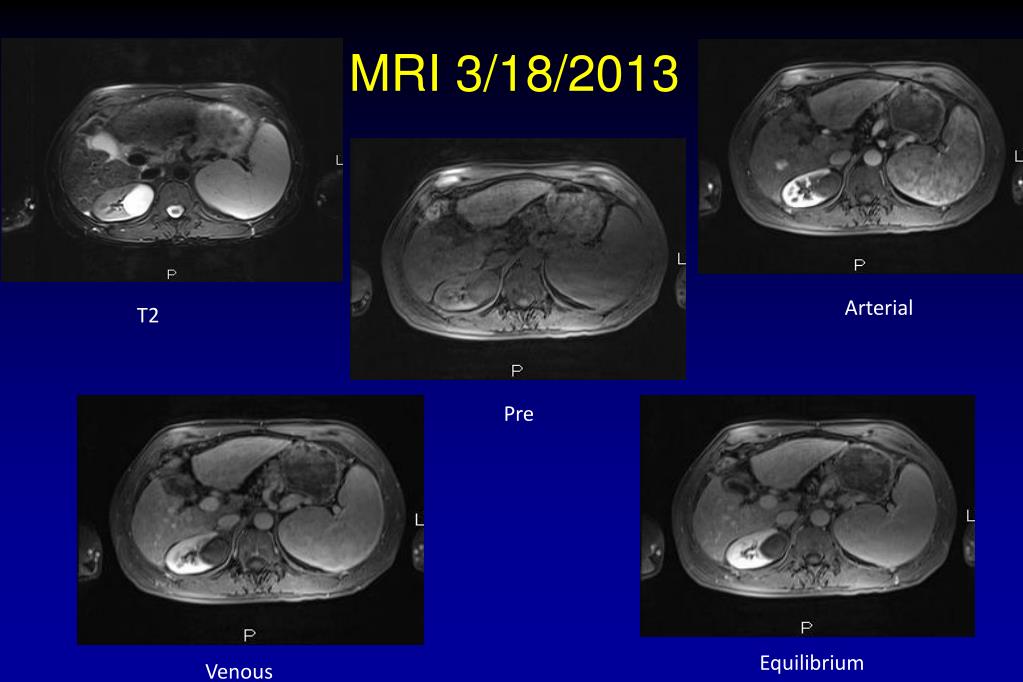

31. MRI 3/18/2013 Arterial T2 Pre Equilibrium Venous